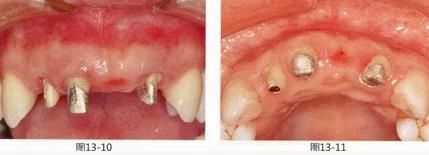

圖13-1   在左上1,2,右上1的橋冠位置有牙齦萎縮,橋體與牙槽嵴之間有空隙。另外,右上2牙體挺出,牙頸線不整齊導致美觀上存在問題。

圖13-2  初期治療后,佩戴臨時修復體后的狀態(tài)。將邊緣線設在了牙齦緣上,之后在通過根面覆蓋將左上2,右上2的牙頸線對齊。